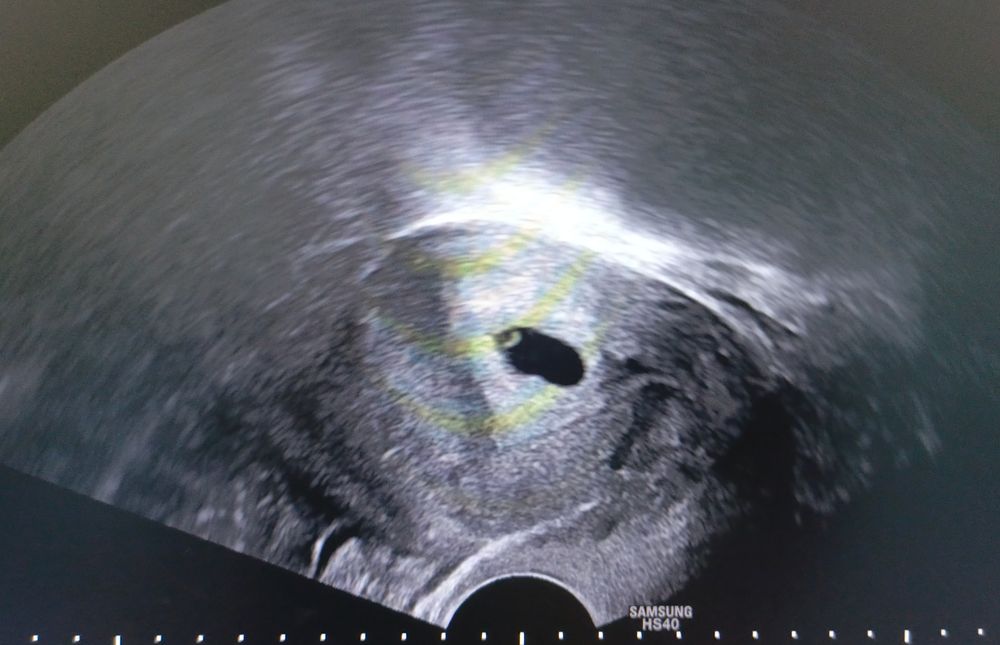

УЗИ, ПЯ деформировано, ЖМ нет

вот как надо не любить людей, чтобы просить у них помощи и не развернуть даже по-человечески фото?) не накручивайте себя раньше времени. При таком диаметре ПЯ нормально, что не виден ЖМ.

Думаю надежда еще есть. ЖМ появляется только когда уже есть эмбрион.

Марина Каралева, через 10 дней лучше переделать узи, должен быть эмбрион и сеодцебиение, плодное яйцо растет по 1 мм в сутки.